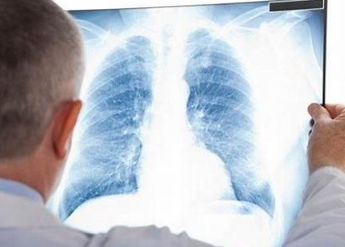

3. 폐결절 발견 방법: 흉부 X-ray, CT 검사

| 요약 | 대개 무증상, 흉부 방사선 촬영과 CT 검사로 발견 |

| 방법 | 흉부 X선 촬영, 흉부 CT 촬영 |

| 특징 | 과거 검사 결과와 비교하여 크기 변화 확인 |

폐결절은 대개 무증상이며, 대부분 흉부 방사선 촬영을 통해 발견됩니다. 최근에는 국가암검진 저선량 CT 검사에서도 폐결절이 발견되기도 합니다. 이는 조기 발견의 중요성을 강조하는 대목입니다.

폐결절의 진단은 주로 흉부 X선 촬영과 흉부 CT 촬영을 통해 이루어집니다. 흉부 X선 검사에서는 과거 검사 결과와 비교하여 결절의 크기 변화를 확인합니다. 이를 통해 결절의 성장 속도와 성격을 파악할 수 있습니다.